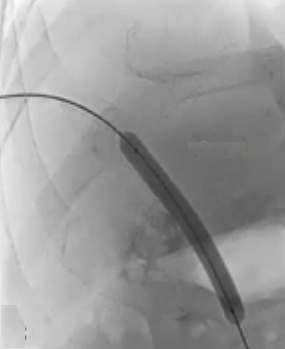

急性门静脉血栓(续) 对于那些成功实施经颈静脉经肝到达门静脉内急性血栓内,并进行了溶栓和抗凝治疗的患者,是否应该进行经颈静脉肝内门体分流术(TIPS)呢(放支架)? 这一问题存在争议。 。一个过于激进的TIPS手术,导致门静脉分支没有血流,从而发展成肝硬化 妥协的操作是设置一个“小TIPS”,即放置一个直径较细(直径5毫米左右)的TIPS裸支架,溶栓导管经支架通过,进行抗凝和溶栓治疗后,同时保留 TJ 对 SMV/PV 的访问权限,以防再次发生血栓情况。 一例术后急性门静脉血栓病例,最终影像显示门静脉根部血流情况良好,这还不够理想,担心会再次发生血栓,且门静脉压(PSG)超过 12 毫米汞柱,因此增加了经导管动脉溶栓术(TIPS)的治疗方案。

在进行门静脉血栓治疗时施行经皮穿刺取栓术所增加的额外风险主要是由于创伤所致。 从技术层面来看,要穿刺进入血栓形成的血管是相当困难的,而且有可能会反复出现成功与失败的情况。 降低风险的方法包括对静脉瓣进行成像,或者安装一个装置来引导穿刺操作。

通过经皮经脾路径具有显著优势,能够使用 4Fr 细导管和导丝进行逆向再通操作,以 10 毫米的圈套器作为经颈静脉穿刺目标,通过Avitene 完成经颈静脉门静脉穿刺。

门静脉血栓TIPS并发症

无论是在急性病例还是慢性病例中,如果能够成功置入一个稳定且有覆膜的经颈静脉肝内门体分流术(TIPS)支架,那么并发症及其影响都会得到减轻。 任何腹腔内的出血都应得到控制(除非是由于腹主动脉损伤所致) 缓解门静脉高压,减少静脉曲张引起的出血。关于“清除”门静脉的各种方法本站在其它栏目已经有所介绍。